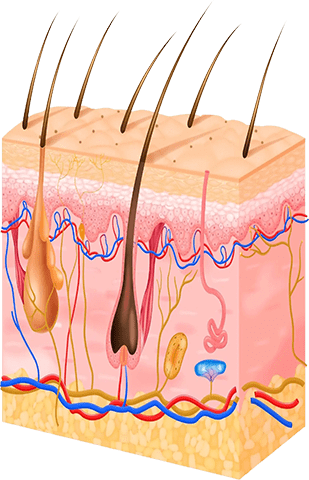

Dermatolojik yapıyı koruyarak donör bölgeden elde edilebilecek maksimum greft sayısını hedefliyoruz.

Eklenecek saçlar en güçlü, en kalın, en çeşitli ve en renkli olduğu için en doğal ve hacimli sonuçları elde edebiliyoruz.

FUE (Folküler Ünte Ekstraksyonu) ile saç kökler ilgili her alan içn ayrı ayrı çıkarılır. Bu şeklde en doğal sonuçları elde ederiz.